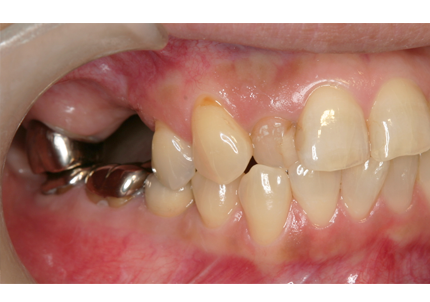

5.右上遊離歯肉移植術(F.G.G)

6.補綴物作製(2010年4月)

7.補綴物装着(2010年5月)